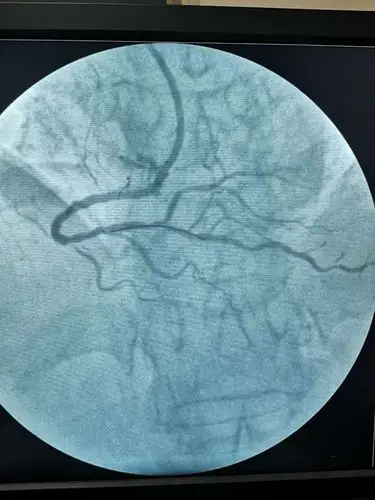

全脑血管造影术 冠脉造影术1例

清晰的心脏冠脉造影图片!

冠脉造影术——叶县二院介入科

冠状动脉造影,左冠状动脉造影,左前降支狭窄.

冠状动脉造影,左冠状动脉造影